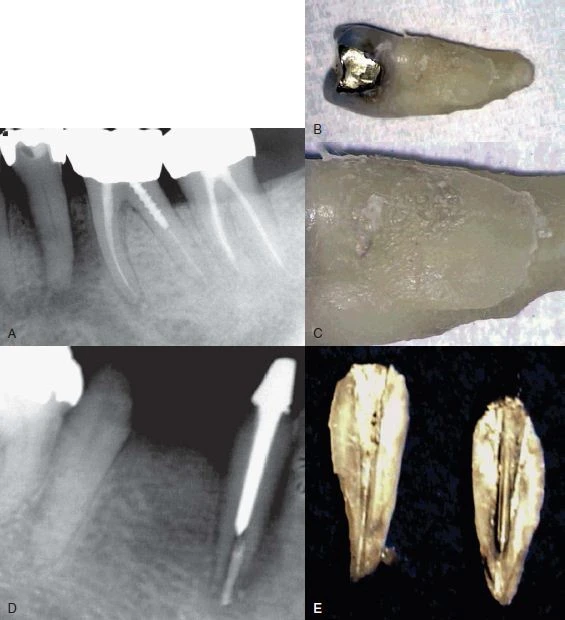

Hình 3. Nhiễm trùng tuỷ răng tái phát sau điều trị nội nha có thể là do nứt dọc chân răng

Hình 9. Đôi khi không có dấu hiệu rõ ràng cho thấy lý do răng có triệu chứng. (A) Hình ảnh X quang cho thấy răng cối lớn thứ hai hàm dưới có miếng trám sâu mức độ trung bình. (B) Thử tuỷ cho thấy răng chết tuỷ. Không chiếu sáng nên không thấy có đường nứt nào cả. (C) Chiếu ánh sáng có cường độ cao lên bề mặt răng, quan sát thấy vết nứt ở mặt ngoài. (D) Chiếu sáng vào mặt xa – trong của răng.

Hình 10. Nứt dọc chân răng dẫn đến chia đôi chân răng, điều này có thể phát hiện dược trên X quang

Hình 11. Mặc dù nứt dọc chân răng không phải lúc nào cũng thấy được trên X quang nhưng với một góc chụp đúng thì có thể quan sát rõ đường nứt.

Đường xi măng

Nứt dọc chân răng hoặc chia chân răng có thể mở rộng thừ mặt gần đến mặt xa của răng, thường đường nứt này xảy ra sau khi thực hiện điều trị nội nha. Đôi lúc sẽ thấy một hình ảnh “đường xi măng” dọc hoặc băng ngang qua chân răng. Phần xi măng bị đẩy qua đường nứt, sau đó có thể thấy được trên X quang. Nha sĩ có thể nhầm với hình ảnh phần xi măng bị đẩy qua ống tuỷ phụ, nhưng trong trường hợp nứt răng thì phần xi măng sẽ bị đẩy ra khuêch tán hơn và không có hình ảnh ống tuỷ bên đổ ra từ ống tuỷ chính.

Hình 12. Hình ảnh “đường xi măng”

Hình ảnh mất xương như “vòng sáng”

Thông thường khi một răng chết tuỷ thì hình ảnh X quang của nó sẽ thay đổi, mất xương xảy ra ở vùng chóp. Tuy nhiên, khi một răng bị nứt dọc hoặc chia chân răng, vùng mất xương có khuynh hướng cho hình ảnh “vòng sáng”, thấu quang xung quanh chân răng. Vùng thấu quang cũng có thể đi dọc toàn bộ một bên chân răng và thường được gọi là tổn thương “dạng chữ J”.

Hình 13. Hình ảnh tiêu xương “dạng chữ J”